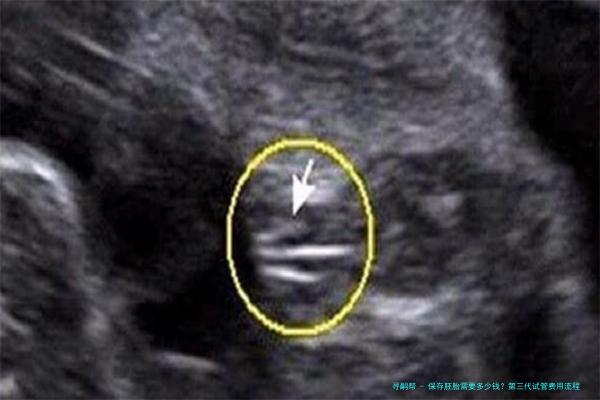

保存胚胎是指将多余的胚胎储存在液氮中,使其处于低温状态,可以长期保持其活力。保存移植技术已广泛应用于临床,为许多不孕夫妇孕育健康婴儿提供了新的机会。在中国大陆保存胚胎的费用因医院和地区而异,通常在3000元至8000元不等。其中较高的金额约为10000-25000元,具体价格取决于医院等因素。

在中国大海保存母细胞个体复苏的费用因医院和区域而异,一般在五千元至20000元不等。详细价格由不同医院确定。该本钱将考虑多个因素,例如超声检查、促排卵的手术支持、稀释步伐和创造(即ICSI)、培育、裂解团体等,以及控制和治疗的支持项目。为了精确取得信息,请咨询您所在地区的相关诊所或门诊付款结算账目处。